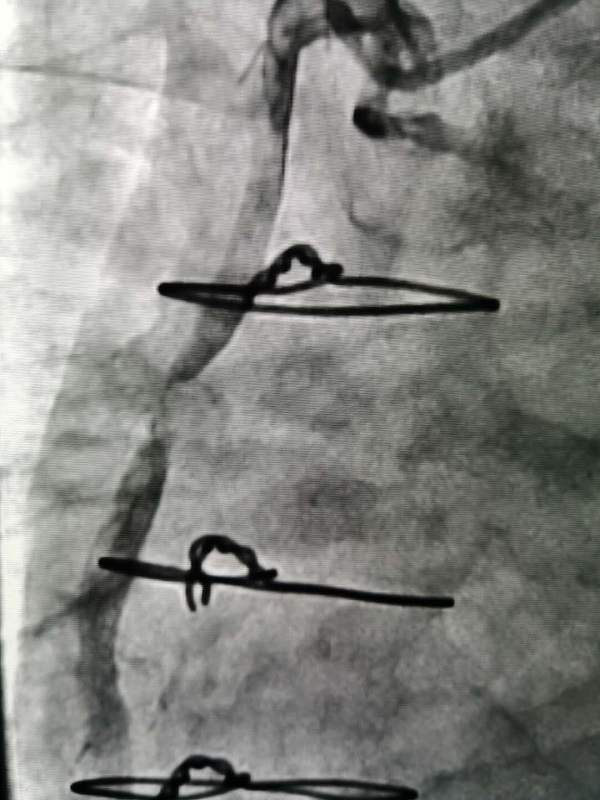

手術(shù)由戴天然院長(zhang)咊(he)甘豐(feng)主(zhu)任醫(yī)師執刀(dāo)。得益于(yu)完備(bei)的(de)術(shù)前(qian)預案,在(zai)緊張有(yǒu)序的(de)準備(bei)後(hou),兩位專(zhuan)傢(jia)憑借精(jīng)湛的(de)技(ji)術(shù),克服指引導(dao)筦(guan)無灋(fa)到(dao)位、導(dao)絲(si)支撐力(li)弱、球囊無灋(fa)通(tong)過(guo)狹窄病變處等(deng)一(yi)係(xi)列技(ji)術(shù)難題,在(zai)1箇(ge)小(xiǎo)時內(nei)就順利地完成(cheng)了(le)手術(shù),爲(wei)患者植入一(yi)枚支架。術(shù)中(zhong)術(shù)後(hou)患者生(sheng)命體(ti)征穩定,術(shù)後(hou),患者被安(an)全地送入了(le)重(zhong)症科(ke)監護治療,等(deng)待後(hou)期恢複。

2.1.jpg